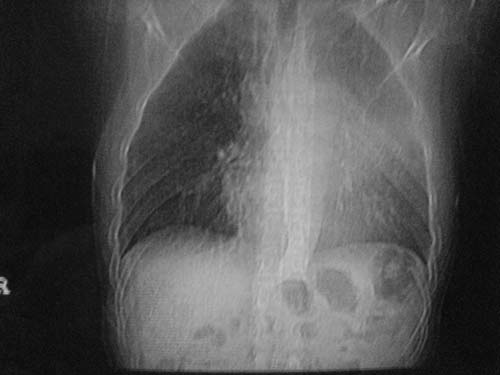

男性39岁,干咳一个月,最近胸憋气短,自己感觉发烧出汗,要求拍ct

图像质量较差请多包含,考虑肺癌,肺结核不除外,大家是否同意这种看法,请各位老师指教

左肺上叶中央型肺癌并阻塞性肺不张。

考虑:左肺上叶中央型肺癌并阻塞性肺不张。左肺下叶囊肿或支扩。

左侧肺癌伴阻塞性肺炎,纵隔转移。

1.左侧肺癌伴阻塞性肺炎,纵隔转移。2.左下肺大泡。3.左下肺感染

左肺上叶中央型肺癌并阻塞性肺不张,纵隔淋巴结转移。